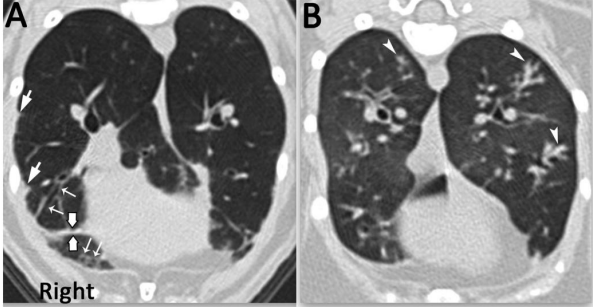

O espessamento intersticial subpleural ocorre nas regiões periféricas do pulmão, ao longo de fissuras ou onde o pulmão toca a parede torácica ou o mediastino, e pode ter uma textura irregular, lisa ou nodular (figura 3). Já o espessamento intersticial peribroncovascular reflete o aumento da densidade nas áreas ao redor das paredes das vias aéreas e artérias pulmonares, desde o hilo até a região periférica do pulmão. Diferenciar o espessamento intersticial peribroncovascular do aumento primário da parede brônquica ou do alargamento dos ramos da artéria pulmonar pode ser desafiador, mas essa distinção é crucial em humanos para diferenciar distúrbios das vias aéreas (como bronquiectasia) de distúrbios que afetam o interstício pulmonar (como doenças pulmonares intersticiais e disseminação linfangítica de carcinoma) (MASSEAU e REINERO, 2019).

Uma faixa parenquimatosa refere-se a uma opacidade linear espessa e longa que geralmente começa na superfície pleural, atravessando o tecido pulmonar, sem delinear uma estrutura anatômica específica (figura 3). O padrão em favo de mel, indica destruição de tecido, substituição por fibrose e distorção da arquitetura pulmonar. Cistos em favo de mel variam em tamanho (geralmente 3–10 mm), têm paredes bem definidas, devem ser múltiplos (pelo menos 3), cheios de ar e geralmente ocorrem em aglomerados ou fileiras (WEBB et al., 2015).

Figura 3: (A) gato com distúrbio bronquiolar primário, com espessamento intersticial subpleural (setas de cabeça grande), linha de fissura pleural espessada (setas grossas) e vias aéreas de pequeno calibre espessadas e dilatadas, sugestivo de broquiolectasia (setas pequenas). (B) padrão de árvore em botão, pequenas vias aéreas preenchidas com atenuação de tecido mole ou fluido, sugestivo de distúrbios bronquiolares.

Fonte: Masseau e Reineroa, 2019